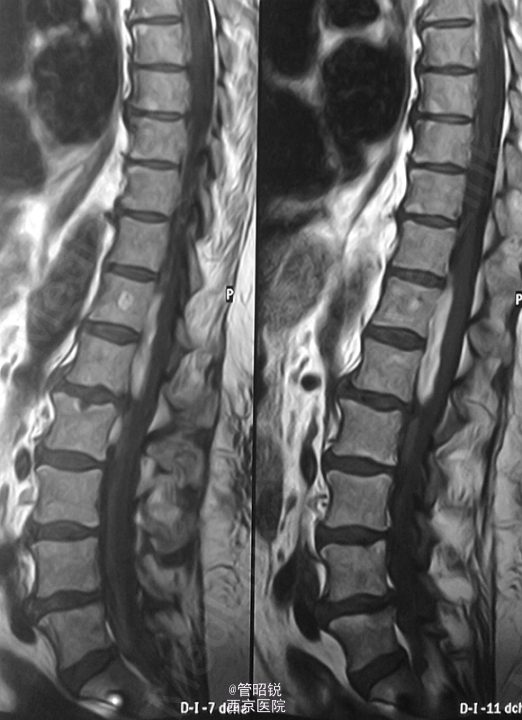

患者,男,71岁,急性头痛和腰痛。 慢性脊髓囊性蛛网膜炎是蛛网膜下腔出血的罕见并发症。此并发症被认为是由于溶血导致的蛛网 膜炎性反应,导致其纤维化和脊膜的继发性增厚,包括硬脑膜。纤维可形成囊腔包裹脑脊液,从而压迫脊髓,引起脊髓病和脊髓空洞积水征。一般保守治疗或者手术 CT显示轻微的脑室内出血,另外,在部分脑裂出可见模糊的高密度影,提示蛛网膜下腔出血。DSA双侧大脑前动脉狭窄。T1WI显示胸腰段脊髓腔内出血,定位在蛛网膜下。随访2年后,显示蛛网膜下的腔隙在脊髓表面形成扇贝样改变。随访3年腔隙仍然存在,以致脊髓表面继发性畸形。(来源于AJNR)